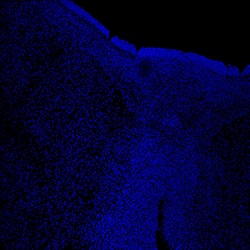

12PCW

DAPI

13PCW human midbrain